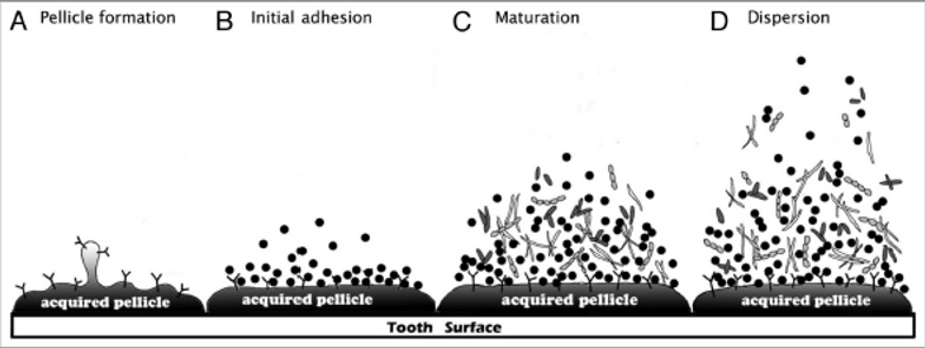

Zapalenie dziąseł inaczej gingivitis spowodowane jest obecnością płytki nazębnej, która jest czynnikiem zapalenio-twórczym.

Wczesne zapalenie dziąseł rozpoczyna się już po 48h, a po 3 dniach pojawia się zapalenie dziąseł, któremu towarzyszą objawy:

Po 7 dniach zapalenie dziąseł wchodzi w fazę przewlekłego brzeżnego zapalenia. Wcześniejsze objawy nasilają się, a naciek zapalny powiększa i staje się intensywniejszy, a szczelina dziąsłowa powiększa się.

Bakteryjna płytka nazębna, która tworzy się na powierzchniach zębów oraz uzupełnieniach protetycznych (ruchomych czy stałych) jest uważana za najważniejszy czynnik miejscowy, który powoduje zapalanie dziąseł . Płytka nazębna umiejscawia się w okolicy szyjki zęba i w przestrzeniach między zębami/ koronami/implantami.

Natomiast już po około 3 dniach zaczyna mineralizować w kamień nazębny, który staje się niemożliwy do usunięcia codziennymi zabiegami pielęgnacyjnymi.